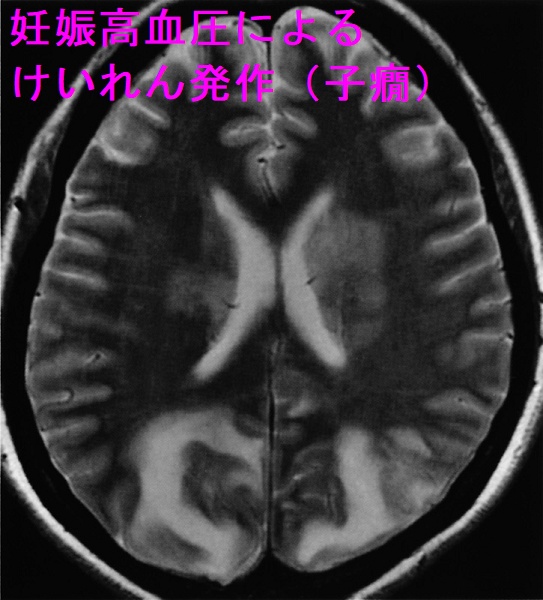

- 母体は妊娠高血圧、蛋白尿、子癇前症→けいれん発作(子癇)、脳出血、肝障害、腎障害、HELLP 症候群(ヘルプ症候群)、急性妊娠脂肪肝

重度の妊娠高血圧腎症(血圧160 mmHg/110 mmHg以上かつ蛋白2+など)では子癇予防のため、硫酸マグネシウム投与が推奨されます。